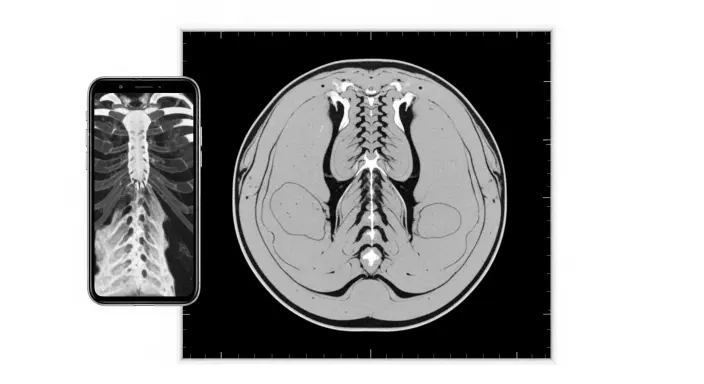

A CT scan (short for computed tomography) creates detailed cross-section images of your organs, bones, blood vessels, and soft tissues.

Instead of showing just one flat image like a traditional X-ray, a CT scan takes multiple images from different angles and combines them into clear, cross-section views.

Think of a CT scan as looking at your body slice by slice. Each “slice” shows bones, organs, blood vessels, and soft tissues in much greater detail than standard imaging tests.

A CT scan provides a detailed look at the structures inside your body, making it one of the most powerful imaging tools available.

Unlike a standard X-ray that mainly shows bones, a CT scan can reveal bones, soft tissues, organs, and blood vessels all at once.

CT scan results can seem confusing at first because they are made up of shades of black, white, and gray, rather than a typical photograph.

These images represent different types of tissues: bones appear white, soft tissues appear in shades of gray, and air or fluid-filled spaces show up as black. This contrast helps doctors quickly identify abnormalities.